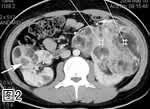

图2. 增强CT扫描

图3. 增强CT冠状位多层面重组像,示双肾巨大肿物,密度不均,可见多发脂肪密度灶(箭号)。肝内亦见一脂肪密度灶(箭头)。